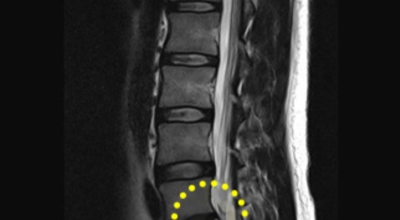

가장 대표적인 증상은 허리를 앞으로 숙였을 때 동반하는 통증으로 디스크 특성상 훼손이 발생하면 후방쪽이기 때문에 이는 허리를 앞으로 숙이면 압박이 심해짐과 또한 통증이 나타나기 때문이라고 하네요. 물건을 줍기 위해 허리를 숙였을 때, 집안일을 하다가 허리를 숙였는데 지속적인 통증이 있다고 하며 압박이 있다면 이는 허리디스크 증상일 확률이 매우 높다고 합니다.

허리디스크 증상 - 기침 재채기를 할 때도 느껴지는 통증

마지막으로 주시해야 할 것은 기침이나 재채기 처럼 허리와 전혀 상관없는 부위의 활동으로도 허리디스크 증상을 의심해 볼 수 있겠습니다. 대개 기침이나 재채기를 하면 우리 상반신 신체 전체를 움직임을 동반하는데 이 경우에 허리에도 쇼크이 고스란히 전해진다고 해요. 이 때에 미세하지만 갑작스럽게 통증이 느껴진다면 이는 허리디스크를 의심해보셔야 해요.